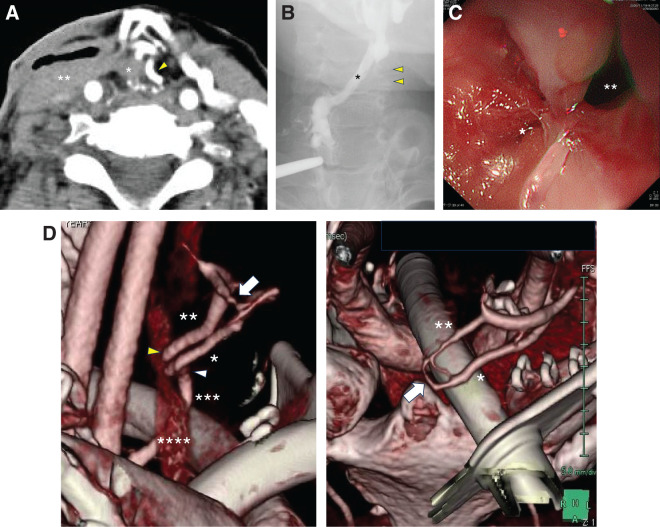

Case presentation: A 61-year-old woman diagnosed with squamous cell carcinoma of the cervical and thoracic esophagus underwent TPLE with gastric conduit and free jejunal graft reconstruction. The third jejunal artery and vein were anastomosed to the left transverse cervical artery and the internal jugular vein, respectively. On postoperative day (POD) 9, leakage was observed at the free jejunal-gastric anastomosis. The fistula healed with conservative treatment but a stenosis at the pharyngeal-jejunal anastomosis developed. Endoscopic observation after balloon dilation of the stenosis showed mucosal hemorrhage and ulcer scarring in the jejunal graft. A 3D reconstructed contrast-enhanced CT revealed the presence of an AVF in the free jejunal mesentery despite well-preserved blood flow across the vascular anastomosis. As no local inflammation was observed in the neck, and oral intake was sufficient after balloon dilatation, she was discharged from hospital. Seven months after surgery, she was admitted to our hospital due to obstruction of the pharyngeal-jejunal anastomosis with cutaneous fistula. Based on the disease course and endoscopic findings of the free jejunal graft, she was diagnosed with cutaneous fistula with scarring obstruction following chronic ischemic enteritis, considered difficult to heal with conservative treatment. Total removal of the free jejunum and reconstruction with an antero-lateral femoral thigh (ALT) flap was performed at 8 months after initial surgery. Oral intake was allowed on POD13, and she was discharged in good condition on POD30.

Conclusions: We report here a rare case of late graft failure after TPLE due to chronic ischemia from an AVF in the mesentery of the free jejunal graft. Detailed assessment of mesenteric blood flow by 3D-constructed contrast-enhanced CT is useful and early removal of the ischemic jejunal graft is suggested.